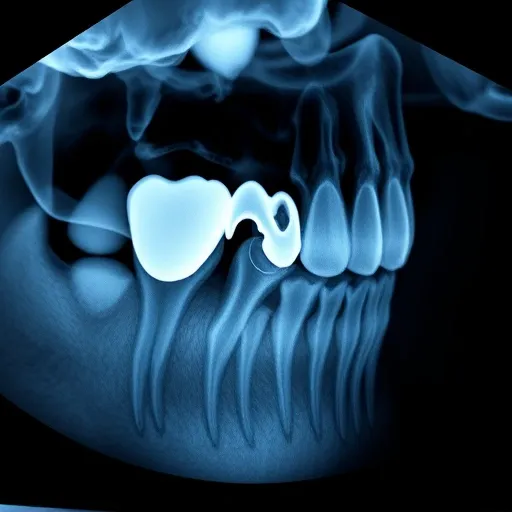

매복된 사랑니가 수평 방향으로 누워 인접한 어금니의 뿌리(치근)를 직접적으로 밀거나 압박하는 경우 발생합니다. 엑스레이나 3차원 CT 촬영을 해보면, 사랑니의 치관(머리 부분)이 어금니의 뿌리 쪽을 깎아내듯이 압박하고 있는 모습을 관찰할 수 있습니다. 이 압력은 치근 흡수를 유발하며, 이는 어금니의 수명과 안정성을 심각하게 저해합니다. 치근 흡수가 일정 수준 이상 진행되면 해당 어금니는 보존이 불가능해져 발치해야 할 수도 있습니다. 이는 단순한 충치와는 달리, 어금니 자체의 구조적 붕괴로 이어지기 때문에 예후가 더욱 좋지 않습니다.

발치와 보존 치료가 동시에 진행되어야 하는 복합적인 상황에서는 무엇보다 정확한 진단 장비가 필요합니다. 2차원적인 파노라마 엑스레이만으로는 사랑니와 어금니 뿌리 간의 정확한 거리와 신경관과의 관계를 파악하기 어렵습니다. 3D 콘빔 CT(CBCT) 촬영은 필수적인데, 이를 통해 사랑니가 어금니를 밀어내는 각도, 손상된 충치의 깊이, 그리고 치근 흡수의 정도를 입체적으로 확인할 수 있습니다. 이러한 정밀 진단 결과를 바탕으로 사랑니 발치와 동시에 어금니 충치 치료를 진행하는 것이 시간적, 경제적으로 가장 효율적인 방법입니다. 만약 치료가 늦어져 어금니의 신경까지 손상되었다면, 신경 치료 전문의와의 협진을 통해 빠르고 정확한 치료를 받는 것이 어금니를 보존할 수 있는 최선의 길입니다.